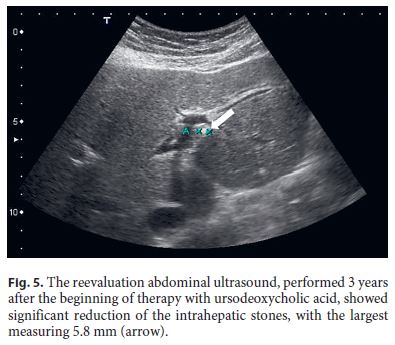

After 3 years of follow-up, the patient is still treated with UDCA and maintains surveillance with blood tests and abdominal ultrasound every 6 months. He remains asymptomatic, has normal liver tests, and his last ultrasound showed significant reduction of the intrahepatic stones (Fig. 5).